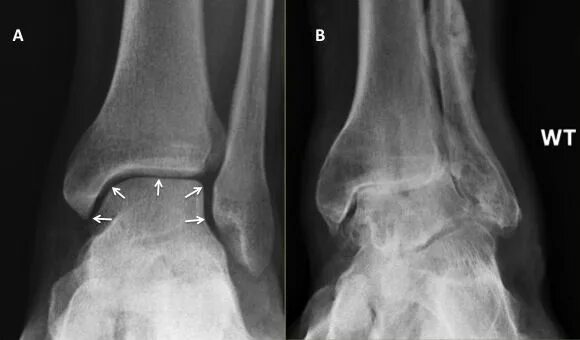

Синовит голеностопного таранного сустава